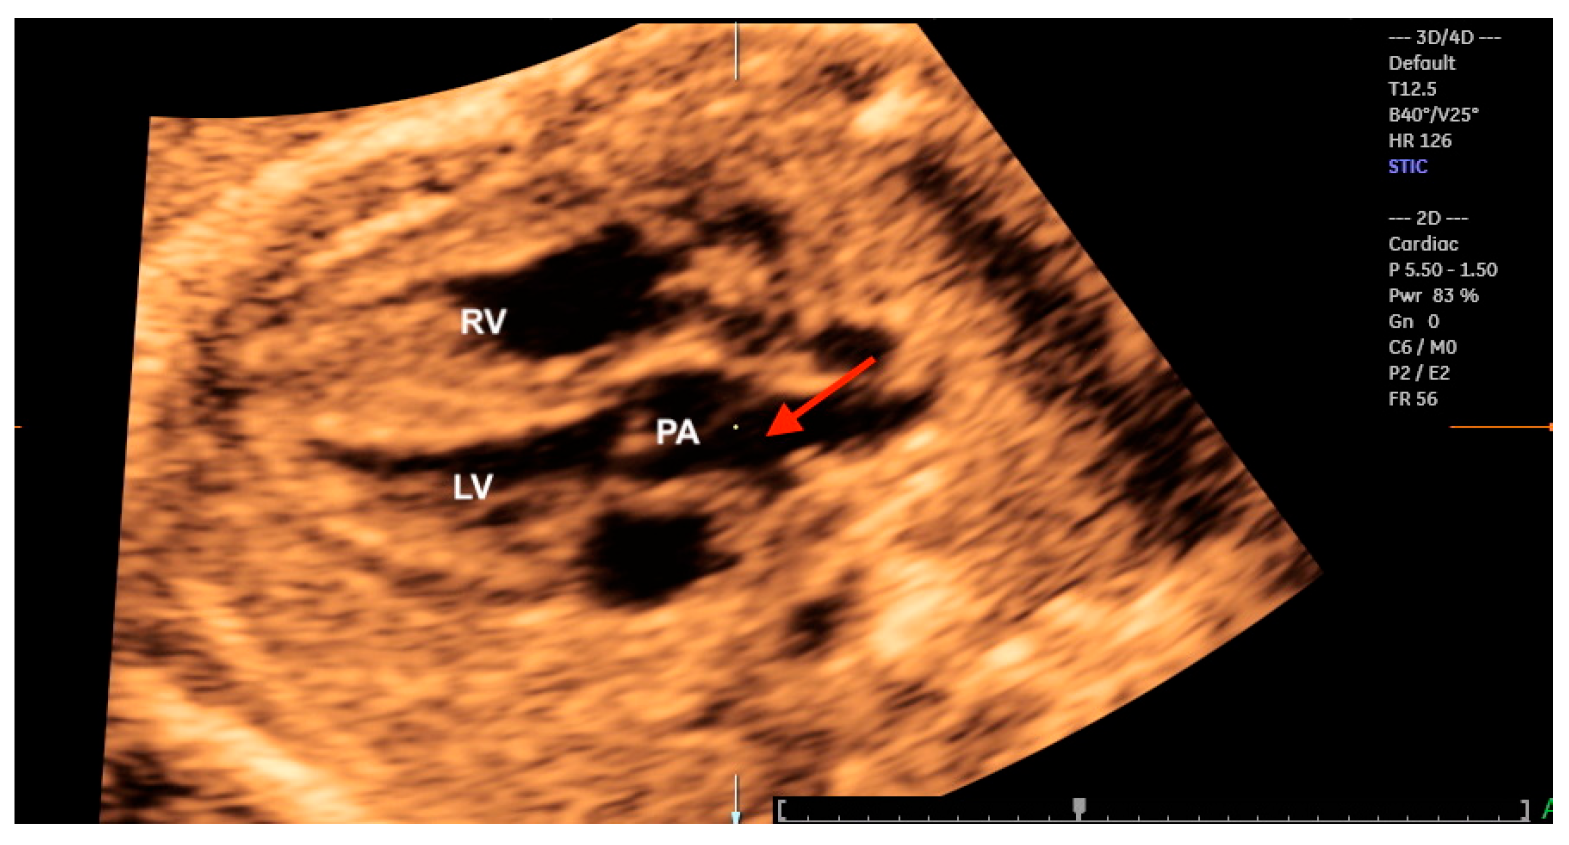

9. Tetralogy of Fallot

10. Transposition of the Great Arteries